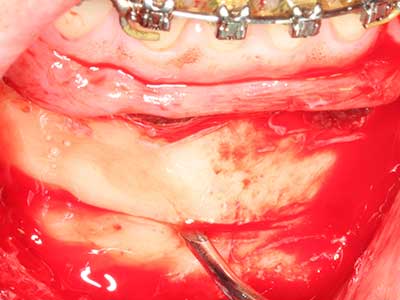

En la extracción de bloques óseos la piezocirugía también presenta ventajas adicionales: Además de la alta precisión en la osteotomía que ya se ha descrito antes, se ha comprobado que el uso de los delgados insertos de sierra resulta especialmente cuidadosas con el hueso. Frente a esto, sobre todo cuando se usan las fresas de Lindemann, cabe esperar pérdidas en la extracción significativamente más altas debido al mayor grosor de la parte frontal del cabezal (Lakshmiganthan, Gokulanathan et al. 2012). La separación basal que se necesita en particular en los injertos de bloque extraídos de forma retromolar se ve facilitada mediante sierras perpendiculares especialmente previstas a tal fin, lo que permite considerar que la cirugía piezoeléctrica es un procedimiento preciso y seguro para la obtención de bloques de hueso en el área retromolar (Happe 2007) (fig. 1-12).

Si es preciso realizar intervenciones quirúrgicas en las que el hueso está en contacto directo con estructuras sensibles, como son los vasos sanguíneos o los nervios, los instrumentos rotativos presentan un enorme potencial de provocar lesiones iatrogénicas. Así, precisamente en la representación de nervios después de una lesión iatrogénica, o en el transcurso de la lateralización de un nervio para resecciones, reconstrucciones o incorporación de implantes, los equipos piezoeléctricos pueden resultar muy útiles para preparar la tapa ósea y retirar las partes de tejido duro cercanas al nervio (fig. 17-20). Por lo general, un ligero contacto del cordón nervioso con el inserto piezoeléctrico no tiene consecuencia alguna; ahora bien, un procedimiento poco cuidadoso con movimientos tipo sierra o piezas de trabajo sobre la base ósea aún existente puede provocar lesiones nerviosas temporales o incluso permanentes. Con todo, el riesgo de sufrir una lesión de este tipo se considera significativamente inferior que en los casos en los que se utilizan sierras y fresas (Pereira, Gealh et al. 2014).